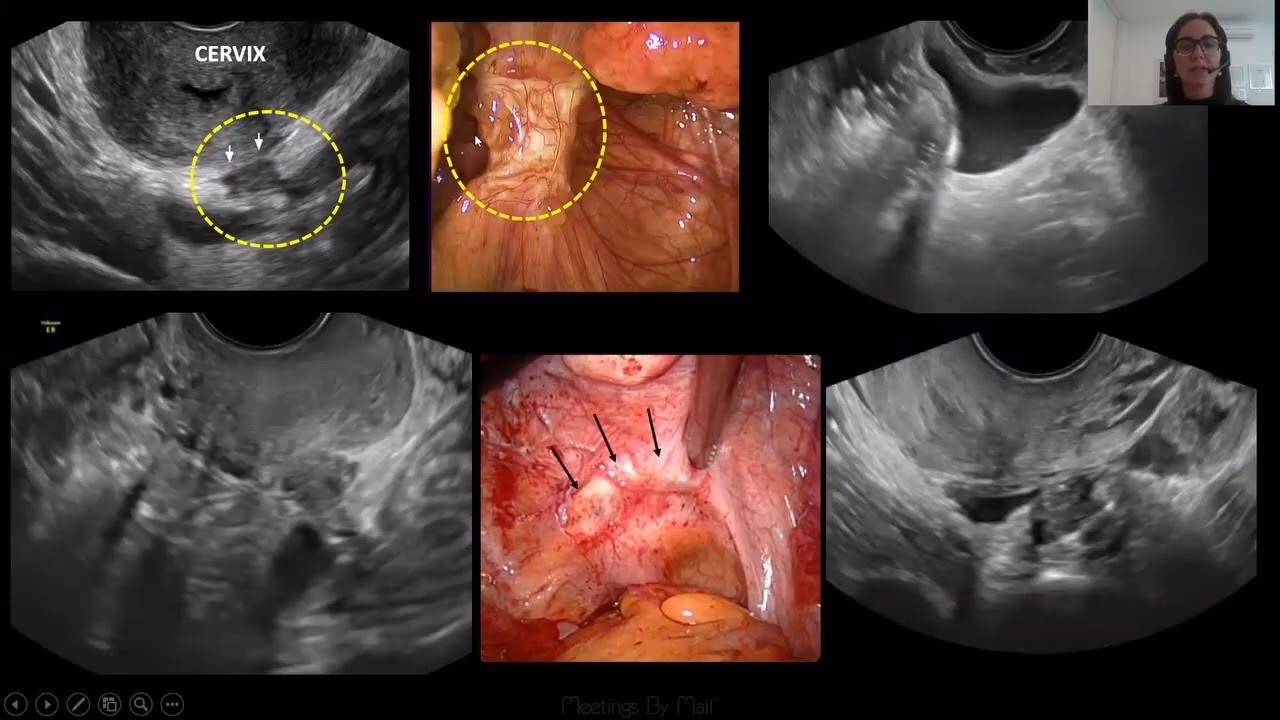

Transvaginal ultralyd

En specialiseret transvaginal ultralyd, udført af en erfaren sonograf eller læge, er et utroligt effektivt værktøj. Den har vist sig at have en sensitivitet og specificitet på over 90% for at opdage dyb infiltrerende endometriose og endometriomer. Under undersøgelsen vurderes ikke kun livmoderen og æggestokkene, men også de forreste og bageste rum i bækkenet. Lægen kan dynamisk vurdere organernes bevægelighed og identificere specifik ømhed. Et vigtigt tegn er det såkaldte "sliding sign". Hvis endetarmen og livmoderen ikke glider frit mod hinanden, indikerer det en sammenvoksning af fossa Douglasi, hvilket er afgørende information for en kirurgisk planlægning.

I mange år blev diagnostisk laparoskopi betragtet som den absolutte "guldstandard" for at stille diagnosen endometriose. Dette er en kirurgisk procedure, hvor en kirurg laver små snit i maven og indsætter et tyndt rør med et kamera (et laparoskop) for direkte at visualisere bækkenorganerne. Kirurgen kan se endometriose-læsionerne, vurdere deres omfang og tage vævsprøver (biopsier) til mikroskopisk analyse for at bekræfte diagnosen.